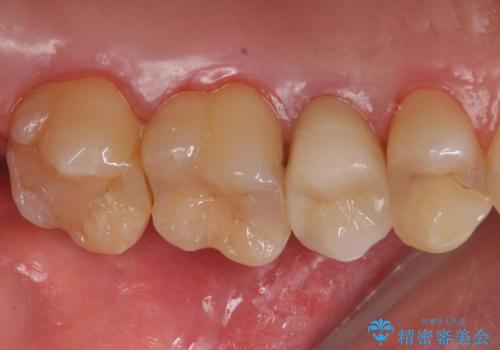

根管内の感染源を可能な限り除去し洗浄しました。

術後は腫れがなくなり特に症状も出ず、メンテナンスに移行しました。